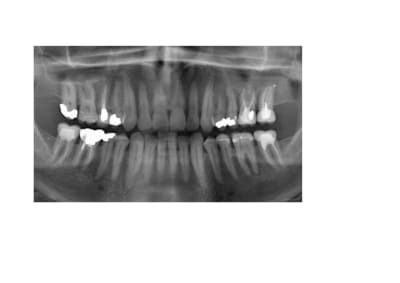

A toutes fins utiles, pour les nouveaux lecteurs, je reposte mes radios.

en ajoutant la 42 également.

4/ la 26 n'est pas claire

Je pense que 3 ans de douleurs inexpliquées çà représente un motif suffisant pour demander un CBCT en haut et en bas aussi, surtout avec autant de dents traitées et retraitées.

C'est marrant que la 37 vous interpelle, alors que la 35 (meme la 45!) est beaucoup plus louche, avec un compo juxta pulpaire (mauvais mariage) , et certainement une mortification lente a bas bruit, le truc bien vicelard au diagnostic differentiel difficile.

Je mets un très gros billet sur une interférence / ou surguidage 6-7

Et retraitement à réaliser sur la 7 car incomplet . Je ne critique pas, ça peut arriver que ça soit très difficile d’accéder jusqu’à l’apex.